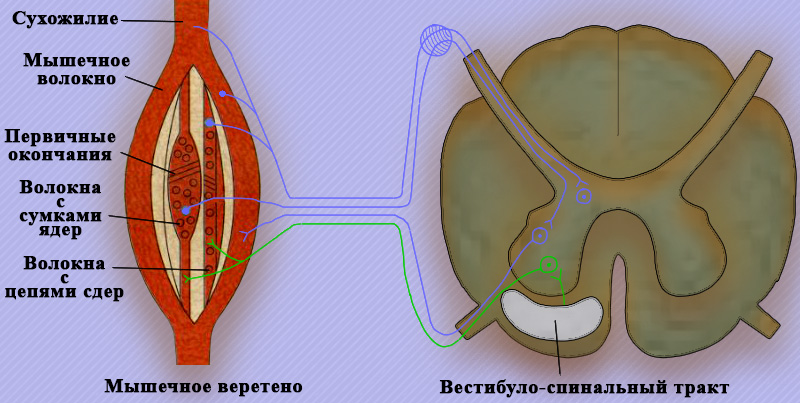

Афферентная часть дуги сухожильного рефлекса растяжения мышц и миотатического рефлекса состоит из быстрых волокон (тип Ia), идущих от мышечных веретен. Быстрые волокна заканчиваются синапсами на клетках передних рогов спинного мозга (отсюда α-мотонейроны направляют нервные импульсы на экстрафузальные мышцы). В свою очередь мышечные веретена иннервируются через фузимоторные волокна (γ-волокна) γ-мотонейронов, обеспечивая поддержание тонуса активных мышц. Стимуляция активности мышечных рецепторов (веретен) при возбуждении гамма-мотонейронов обеспечивает развитие уже начавшегося сокращения (движения).

Афферентные быстропроводящие нервные волокна типа Ib пролегают от рецепторов Гольджи (сухожильных органов). При раздражении этих рецепторов активность α-мотонейронов ингибируется (через один или несколько вставочных нейронов) (рисунок 4).

Рисунок 4. Рефлекторная дуга миотатического рефлекса

Таким образом, активность всех мышц контролируется двумя системами обратной связи: